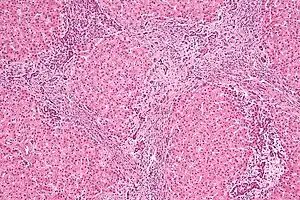

| Micrograph of focal nodular hyperplasia. H&E stain. | |

Focal nodular hyperplasia's most recognizable gross feature is a central stellate scar seen in 60–70% of cases. Microscopically, a lobular proliferation of bland-appearing hepatocytes with a bile ductular proliferation and malformed vessels within the fibrous scar is the most common pattern. Other patterns include telangiectatic, hyperplastic-adenomatous, and lesions with focal large-cell dysplasia.[1] Rarely, these lesions may be multiple or can occur as part of a syndrome with hemangiomas, epithelioid hemangioendothelioma, hepatic adenomas, fibrolamellar hepatocellular carcinoma, vascular malformations of the brain, meningiomas, and/or astrocytomas.[1]